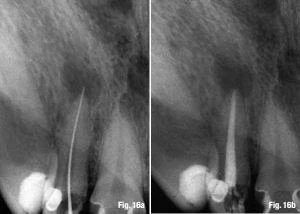

Nếu điểm thắt chóp cách chóp răng 0.5 mm thì 66% là tất cả các dụng cụ đã đi quá nó. Khi file còn cách chóp trên X-quang thì sự thật là nó gần với lỗ chóp hơn so với hình ảnh xuất hiện trên X-quang. Chiều dài làm việc trên X-quang chấm dứt cách chóp trên X-quang từ 0 đến 2 mm nên dụng cụ dễ đi quá chóp mà chúng ta không hề biết, và điều này xảy ra thường xuyên hơn mong đợi. Hình ảnh từ 16a đến 17b là để minh họa những sai lầm trong việc quyết định WL, nó có thể được cải thiện để đạt được thành công cuối cùng.

Quyết định chiều dài làm việc và cách xác định điểm chóp cuối cùng  3

Hình 16a & b: Tình huống lâm sàng với dụng cụ quá chóp (a), sau đó được cải thiện lại bằng việc trám bít ống tủy cách chóp trên X-quang khoảng 0.8 mm.

Quyết định chiều dài làm việc và cách xác định điểm chóp cuối cùng  6

Hình 17a & b: Cải thiện lỗi sai khi quyết định WL (a) và kết quả cuối cùng ít nhiều thành công hơn (b).